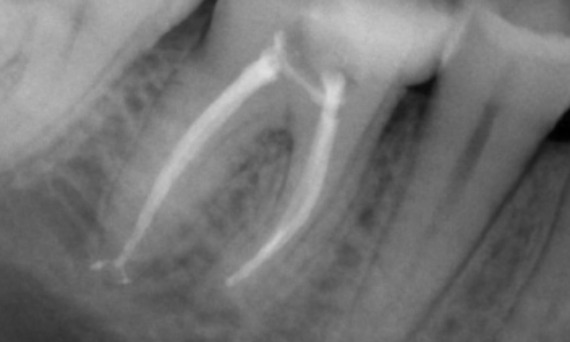

Después: La cavidad de acceso se realizó de la manera más conservadora posible. TruNatomy fue el sistema de elección debido a la edad del paciente joven. Necesitábamos preservar la dentina tanto como fuera posible para aumentar la capacidad del diente y así superar la carga oclusal y aumentar la longevidad de la restauración final.